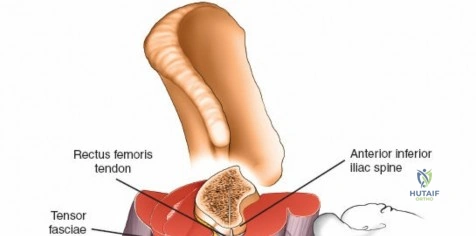

Wrist and Metacarpal Safe Zones

For spanning wrist fixators, distal pins are placed in the second metacarpal. The safe zone is the dorsoradial aspect of the second metacarpal base and shaft. The first dorsal interosseous muscle and extensor tendons must be respected. The radial artery courses proximally in the anatomic snuffbox and must be avoided during basal metacarpal pin insertion.

Metacarpal Pin Placement

1. Make two 1 cm incisions over the dorsoradial aspect of the second metacarpal.

2. Dissect bluntly, protecting the dorsal sensory branches of the radial nerve and the extensor tendons.

3. Place the tissue sleeve at a 45-degree angle to the dorsal and lateral planes to maximize purchase in the metacarpal shaft.

4. Pre-drill and insert two 3.0 mm pins.